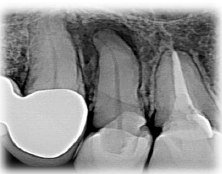

No que tange à radiologia, alguns requisitos devem ser cumpridos para que as tomadas radiográficas realizadas antes e/ou durante as fases do tratamento ou retratamento endodôntico proporcionem imagens capazes de fornecer as informações necessárias. Assim, conforme esses requisitos, analise e julgue as afirmações abaixo:

Machado, Ricardo. Endodontia: Princípios Biológicos e Técnicos. Disponível em: Minha Biblioteca, Grupo GEN, 2022.

I. O filme precisa conter a totalidade da(s) coroa(s), da(s) raiz(es), e de 2 a 3 mm de tecido ósseo saudável recobrindo o(s) ápice(s) ou a imagem patológica periapical. As radiografias panorâmicas ou oclusais devem ser realizadas quando há a necessidade de avaliação de áreas mais extensas.

II. A(s) imagem(ns) deve(m) ter qualidade suficiente para proporcionar análises acuradas da(s) área(s) e/ou do(s) dente(s) de interesse, devendo conter alongamento ou encurtamento.